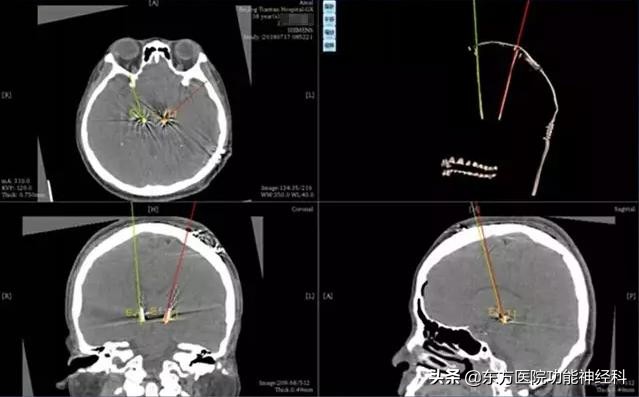

同济大学附属东方医院功能神经科应用机器人定向技术来护航DBS手术,可以让手术完成的更漂亮,更精准。

术后影像与术前规划融合后,测得植入误差<1mm